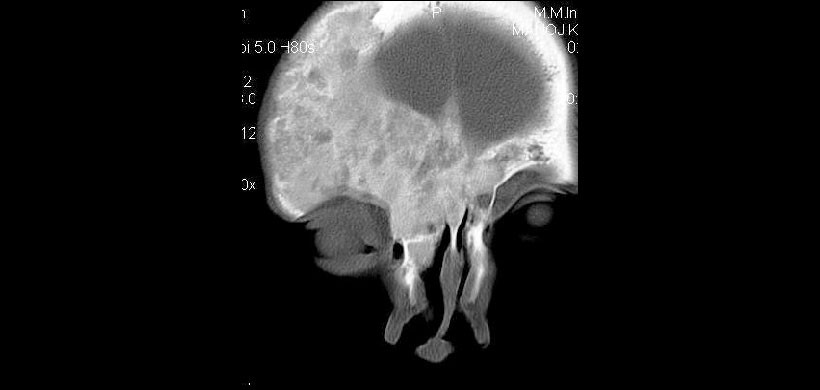

Figura 4: Corte coronal de TC  que revela la lesión que cruza la línea media en la región frontal con afectación de Crista Galli.